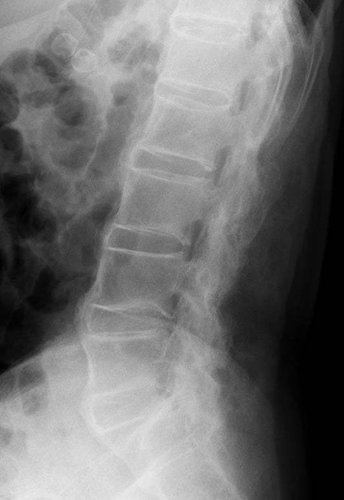

希少難病である強直性脊椎炎は、病変部位では靭帯と骨との付着部位に炎症・骨化が起こり(図1)、疼痛、運動制限等がみられ、重症例では、体軸関節の強直をきたして日常生活能力の著しい低下をもたらします。FPP003は幅広い炎症性疾患に関与するタンパク質IL-17Aに対する抗体を誘導するペプチド治療ワクチンであり、強直性脊椎炎に代表される体軸性脊椎関節炎の新規治療選択肢となることが期待されます。

希少難病である強直性脊椎炎は、腰椎などの体軸関節で靭帯と骨との付着部位に炎症・骨化が起こり、疼痛、運動制限等がみられ、重症例では、体軸関節の強直をきたして日常生活能力の著しい低下をもたらします。FPP003は幅広い炎症性疾患に関与するタンパク質IL-17Aに対する抗体を誘導するペプチド治療ワクチンであり、強直性脊椎炎に代表される体軸性脊椎関節炎の新規治療選択肢となることが期待されます。